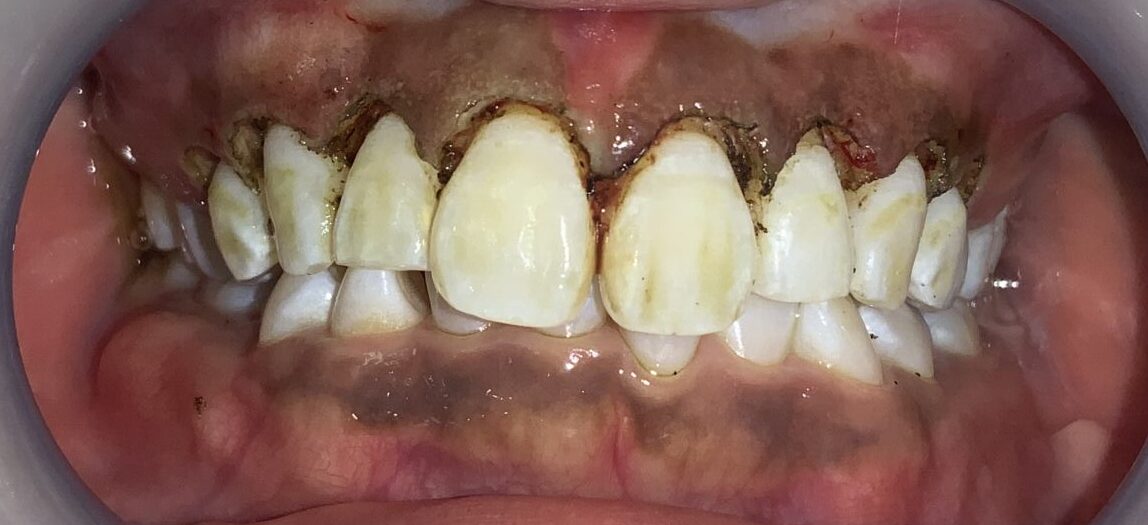

患者様のご希望により、大きめの切除と歯槽骨の整形を行なっています。歯も、歯ぐきも歯槽骨もとてもキレイです。

患者様のOKが出たので、すべての歯の治療を行いました。

歯ぐきの面積が少なくなって、笑った時の歯ぐきが見えなくなり、歯の形も、歯ぐきの形も綺麗に改善しました。

歯ぐきが一部黒ずんでいる部分は、数日で改善するのでご安心ください。